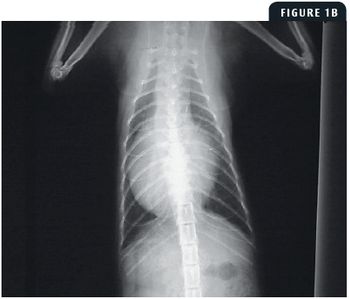

An approximately 1-year-old, neutered male domestic longhaired cat weighing 6.5 lb (2.9 kg) was evaluated by the referring veterinarian because of mild dyspnea.